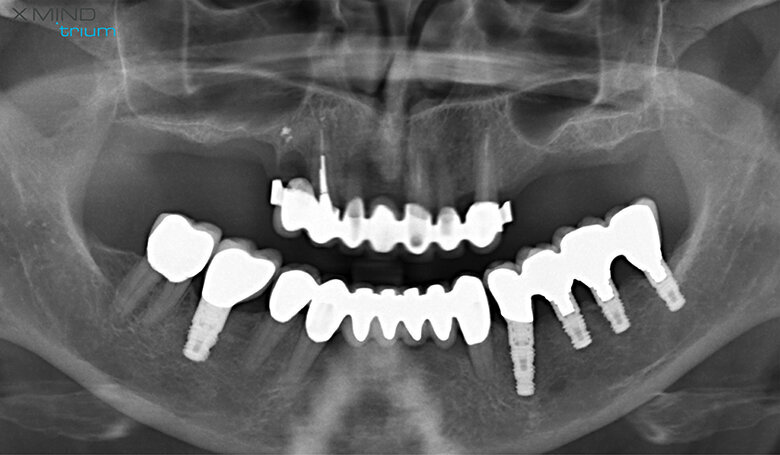

Figure 1 shows a split-mouth case with a bilateral INTRALIFT procedure: after a small crestal “booklet”-flap of approx. 7x7mm is detached, the sinus floor is safely opened with ultrasound Piezotome tips (Figs. 2 & 3), the sinus membrane then detached by the hydrodynamic cavitation effect of the Piezotome-tip TKW5 plugged into the approach canal (Figs. 4 & 5) and the subantral scaffold filled with 2cm of randomly assigned biomaterial (Figs. 6 & 7), followed by wound closure (Fig. 8). After a mean healing period of 8,4 months X-Mind trium CBCT scans were performed, the digital setup of the future bridge constructed with the AIS 3D app and the bone density determined in the sinus-lift site around a virtual implant (Fig. 9). Standardised implants (4mm in diameter and 12mm in length) were then inserted in the position of the virtual implant and insertion torque values (ITV) measured intra-surgically (test groups; Fig. 10). A total of 27 patients with sufficient native subantral crestal bone (min. crest width: 6 mm, height: 12 mm) were screened by X-Mind trium CBCT for bone density with the virtual implant (Fig. 11), the standardised implant inserted and the ITV recorded (control group). Figure 12 depicts the final result after implant insertion in the patient case shown in Figures 1–9.